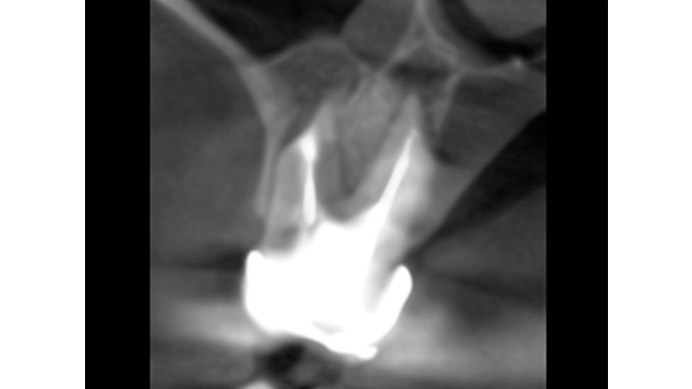

Ian es un paciente que nos cuenta su experiencia tras una intervención de cirugía periapical. Ian vino a la clínica dental IDIM con molestias en una muela superior que en el estudio radiográfico se vio que presentaba infección a causa del fracaso de una endodoncia.

Se decidió realizar una cirugía periapical para eliminar la infección y sellar las raíces con un empaste para evitar que volviera a tener problemas. Gracias a esta efectiva intervención Ian conserva su muela, lo cual es preferible, siempre que se puede, a tener que extraerla y sustituirla con un implante dental.